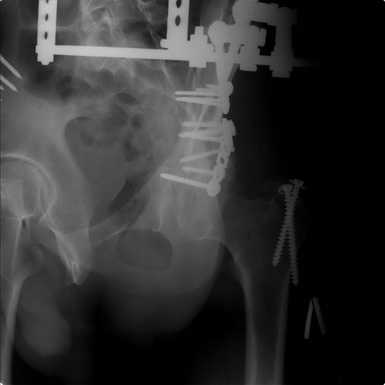

Добрый вечер, уважаемые коллеги. Прошу прощение за долгое молчание( компьютер был в долгосрочном ремонте). Больного с 9-ти месячной травмой таза мы прооперировали. Оценив свои возможности и совместив с вашими рекомендациями и советами (большое спасибо Рункову!), пошли задне-наружным доступом, с отсечением большого вертела. Закрепились 2-мя пластинками. Сверху закрепили аппаратом( передней рамой). На область перелома самого гребня повздошной кости не вмешивались. Снимки высылаю. Жду ваших отзывов и комментариев. Всем большое спасибо за активное участие в лечении больного. С ув.Андрей

Для чего аппарат? Или вы не уверены в стабильности вашей внутренней фиксации? Выглядит достаточно стабильно, аппарат позволит всего лишь чуть ранше дать нагрузку, и всё?

Внутренняя фиксация получилась достаточно стабильная.А передняя рама наложена с целью дополнительной фиксации для нейтрализации мышц прикрепляющихся к крылу подвздошной кости, и исключить возможное расшатывание и возникнование нестабильности внутрених фиксаторов( уж очень большая нагрузка на эти 2 пластины).На открытом этапе операции мобилизовали только часть линии всего перелома( около 1/4 части начиная от свода и проксимально), а остальная часть находится в рубце и патологическая подвижность в ней есть хоть и не выражена) А о ранней нагрузке никто и не думал. А как на ваш взгляд, в какие сроки в такой ситуации разрешить полную нагрузку? Я считаю, что только при сращении перелома, подвержденные лучше бы КТ